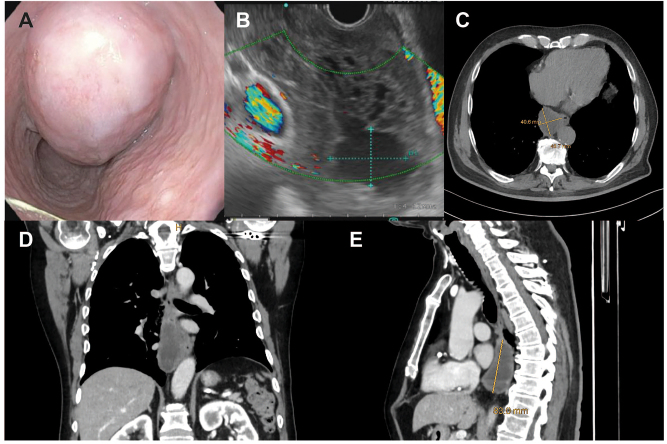

Abstract Image